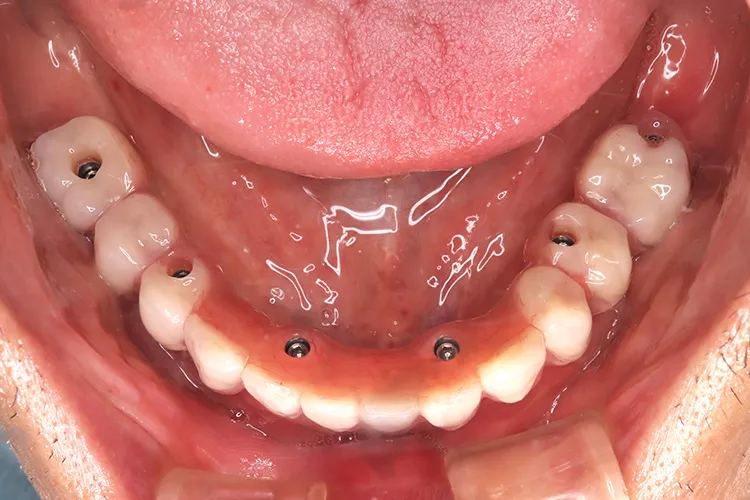

症例8/

下顎ボーンアンカードブリッジ

- 治療期間

- 6ヶ月

- 費用

- 265万円(税込)

治療前

治療後

レントゲン画像

治療内容

ボーンアンカードブリッジの下顎症例です。同じようにインプラント6本で上部構造を支えることができます。